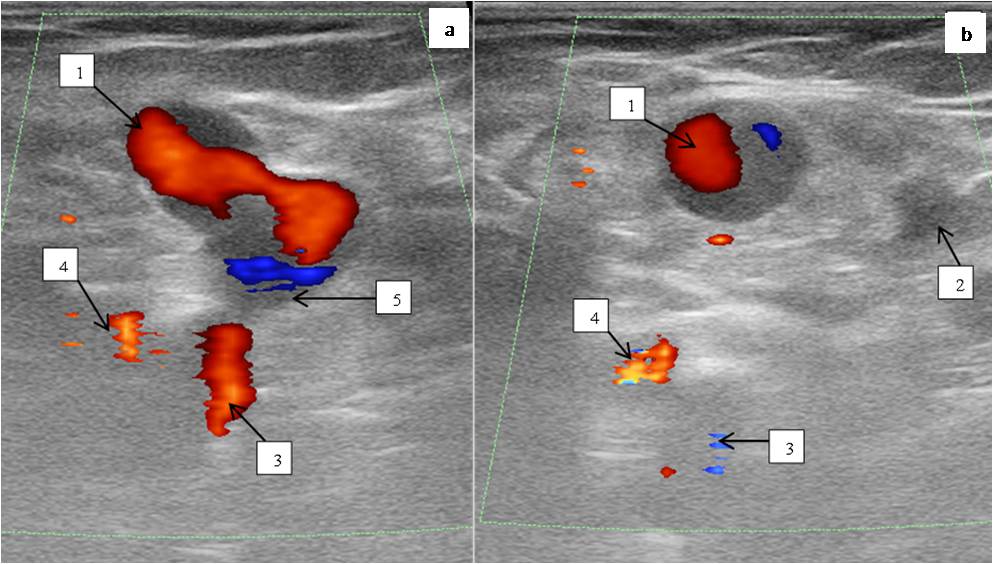

DS of the lower limb veins: deep veins patent, full compression, moderate insufficiency of the common femoral vein valves, other segments of deep veins competent. The SFJ receives the competent GSV and the varicose incompetent anterolateral tributary. SSV patent, competent (Figure 3).

Fig. 3. Female patient Z., 35 years old. US scan of vessels of the saphenofemoral junction at the time of Valsalva test.

Notes: 1 — varicose anterolateral tributary, 2 — great saphenous vein, 3 — common femoral vein, 4 — common femoral artery, 5 — saphenofemoral junction.